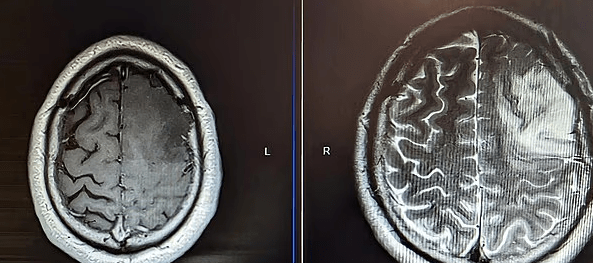

Por ajo që nuk e priste ishte zbulimi i një tumori në tru, sa një dardhë, një gliomë me zhvillim të ngadaltë, që po rritej pa u vënë re.

“Bënë një skanim për të parë nëse kisha gjakderdhje të brendshme ose tronditje, që me siguri e kisha,” – shtoi ai. “Prisja të më thonin diçka të tillë, por në vend të kësaj, më thanë: ‘kemi një lajm të mirë dhe një të keq’. Lajmi i mirë ishte se nuk kishte gjakderdhje, por lajmi i keq ishte se kishin zbuluar një tumor primar në tru.”

Megjithëse mban një qëndrim pozitiv, Connor u detyrua t’i nënshtrohej disa ndërhyrjeve të vështira kirurgjikale. Në shkurt 2023 iu nënshtrua një kraniotomie, ku mjekët hoqën 70% të tumorit. Por operacioni duhej ndalur për shkak të afërsisë me zonën e të folurit në tru – nëse do të vazhdonin, ai do të humbiste përgjithmonë aftësinë për të komunikuar.

Në një kontroll MRI në shkurt, mjekët vunë re zona të reja në tru që ndizeshin gjatë skanimit – kishte një rritje të re. Kjo e detyroi Connor-in të fillojë 6 javë terapi me rrezatim (radioterapi), prej të cilave ai ka kaluar katër, e më pas do të ndjekë një trajtim me kimioterapi – çka e detyroi të largohet sërish nga puna.